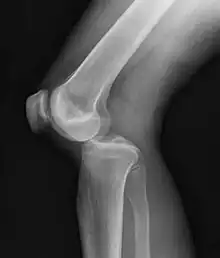

Plain lateral X-ray of the left knee showing a posterior knee dislocation[1]

A knee dislocation is an injury in which there is disruption of the knee joint between the tibia and the femur.[3][4] Symptoms include pain and instability of the knee.[2] Complications may include injury to an artery, most commonly the popliteal artery behind the knee, or compartment syndrome.[3][4][7]